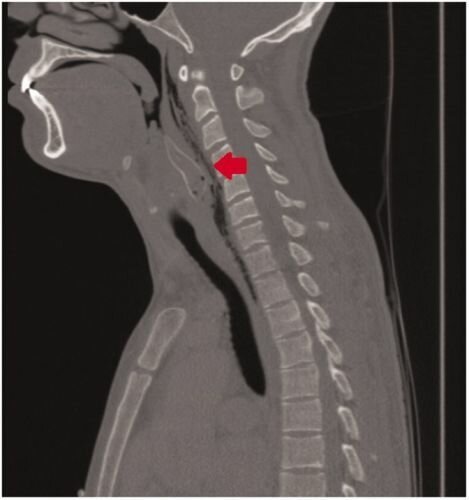

Спустя пару часов, когда все кустарные методы были испробованы, друзья отвезли шутника в ближайшую клинику. Странный пациент не захотел объяснить врачам, в чем причина его бедственного положения и просто жаловался на то, что подавился пищей. Но рентген сразу же показал, что внутри парня находится рыбка и пришлось признаться в исполнении дурацкого трюка.